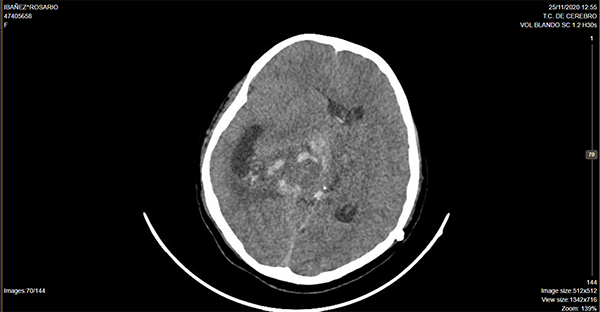

Caso ilustrativo n°2: Houkin tipo 2(Figura 2)

Paciente de 14 años de edad, consultó por deterioro del sensorio, cefalea y vómitos, se realizó tomografía computada de cerebro donde se evidenció lesión ocupante de espacio supratentorial intraventricular. Se programó cirugía, se realizó exéresis parcial. Cursa postoperatorio intubada en terapia intensiva presentado descompensación hemodinámica a las 24 hs, imagen por tomografía computada de cerebro que evidencia sangrado intratumoral, se reexplora la lesión, paciente evoluciona desfavorablemente.

Se consideró Houkin tipo 2, ya que el evento adverso estuvo relacionado con el procedimiento quirúrgico pero no era ni esperable ni evitable.

Figura 2:

Imagen por Tomografía Cerebral computada donde se observa lesión ocupante de espacio intraventricular centroencefálica, con sangrado intratumoral y desvío de línea media.